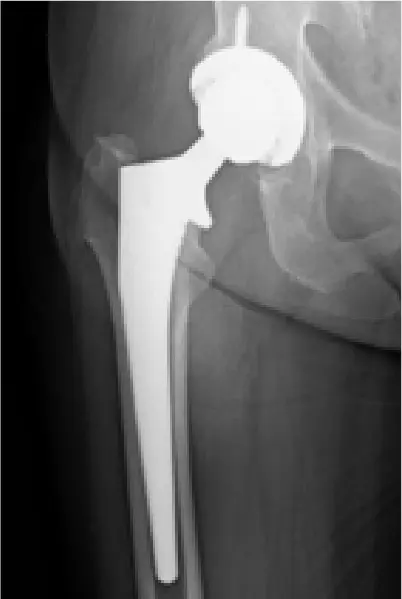

全国の病院では、大腿骨骨折の手術までに平均4〜5日かかるのが現状です。当院では原則48時間以内の手術を目標とし、万全の体制を整えています。大腿骨骨折は「治療の早さ」が回復を左右する重要な疾患だからこそ、これほど手厚く手術室を確保し、患者さんの一日も早い回復を支えます。